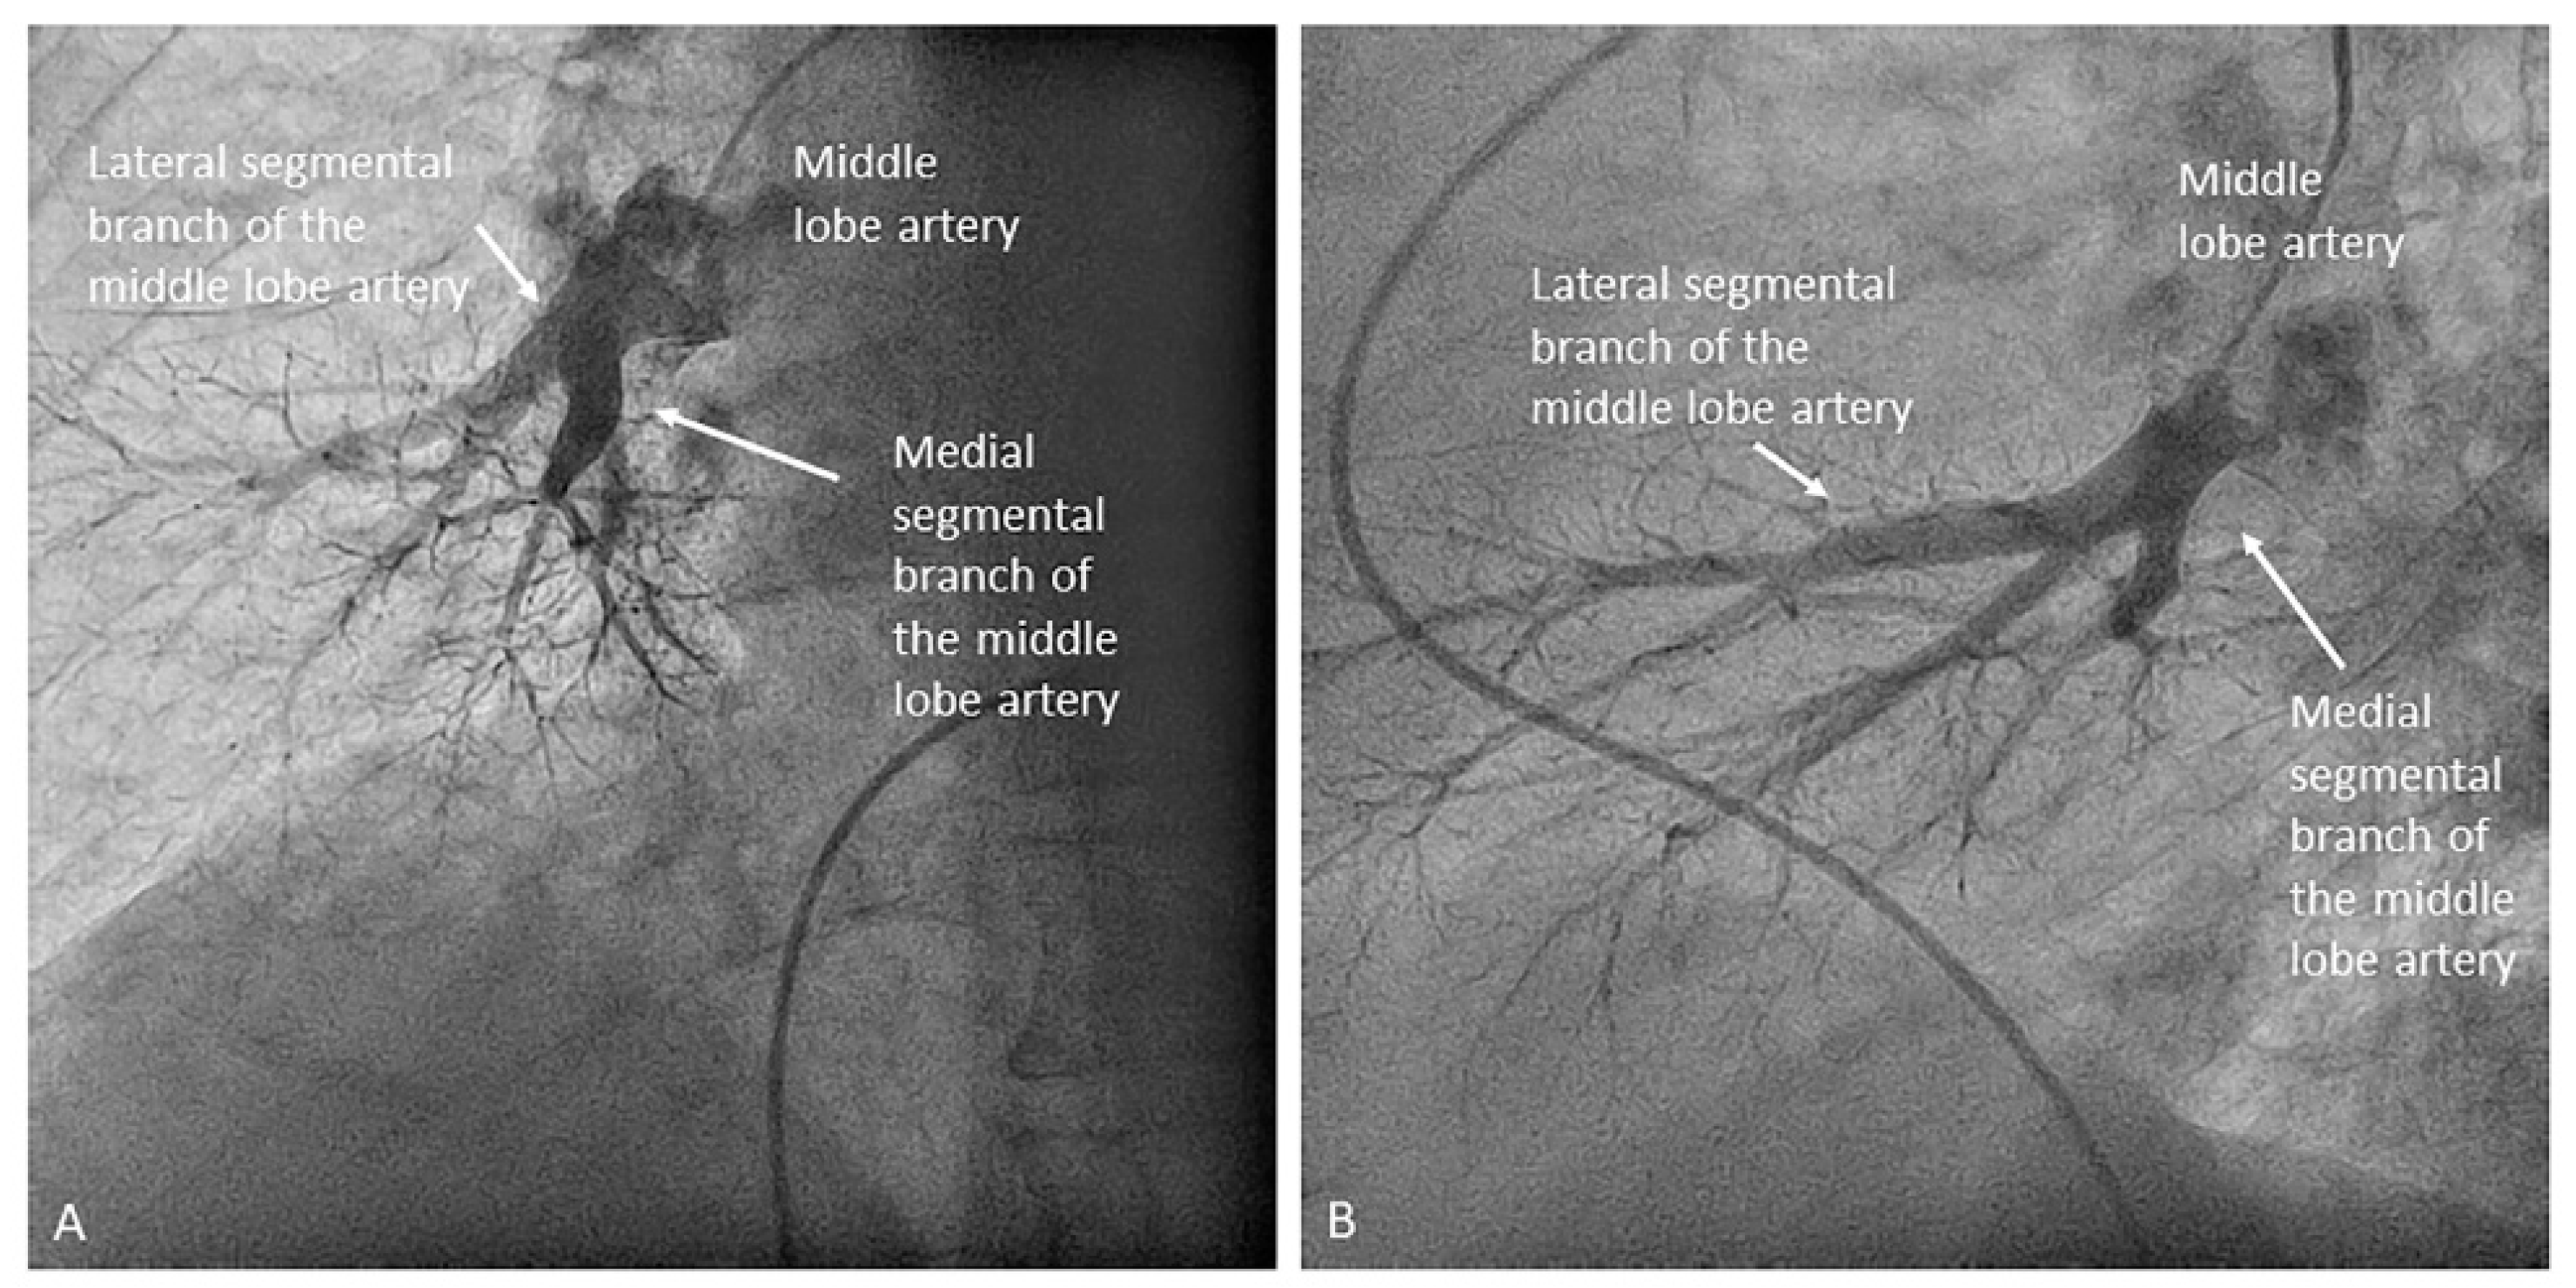

- Middle lobe. The middle lobe artery originates in front of the superior segmental artery of the RLL (A6), with an anterior direction, as does the lingula in the left lung (Figure 14). It is canalized with the MP, in the lateral view. The distal angulated segment of the MP should be bent, pressing against the bifurcation of the RLL, and rotated counterclockwise, with the tip of the catheter pointing towards the sternum (Figure 30). The JR 4 is also a good alternative. This artery bifurcates early in two segmental branches: lateral (A4) and medial (A5). The lateral and cranial LAO views display both branches. If these segmental branches have an independent origin in the RPA, they should be cannulated and filmed independently (Figure 31).